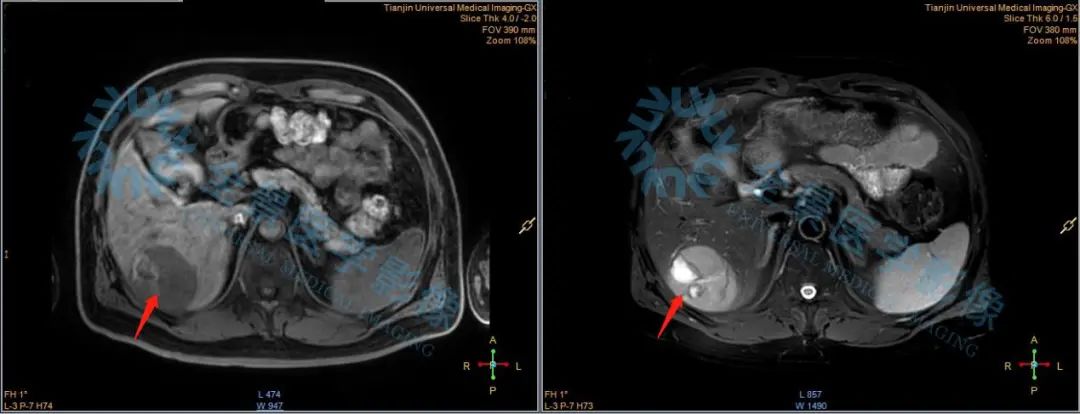

为了给出更准确的诊断意见,医生不但为张先生加扫了肝脏部位磁共振,二者信息融合,还进一步完善患者病史资料的搜集,参阅了患者以往影像检查资料。

磁共振具有无辐射、组织分辨率高、多方位成像优势。多参数MRI对直径≤2cm肝癌的检出和诊断能力优于动态增强CT,在评估肝癌对门静脉、肝静脉主干及分支,腹腔或腹膜后间隙淋巴结转移方面具有优势。[9]